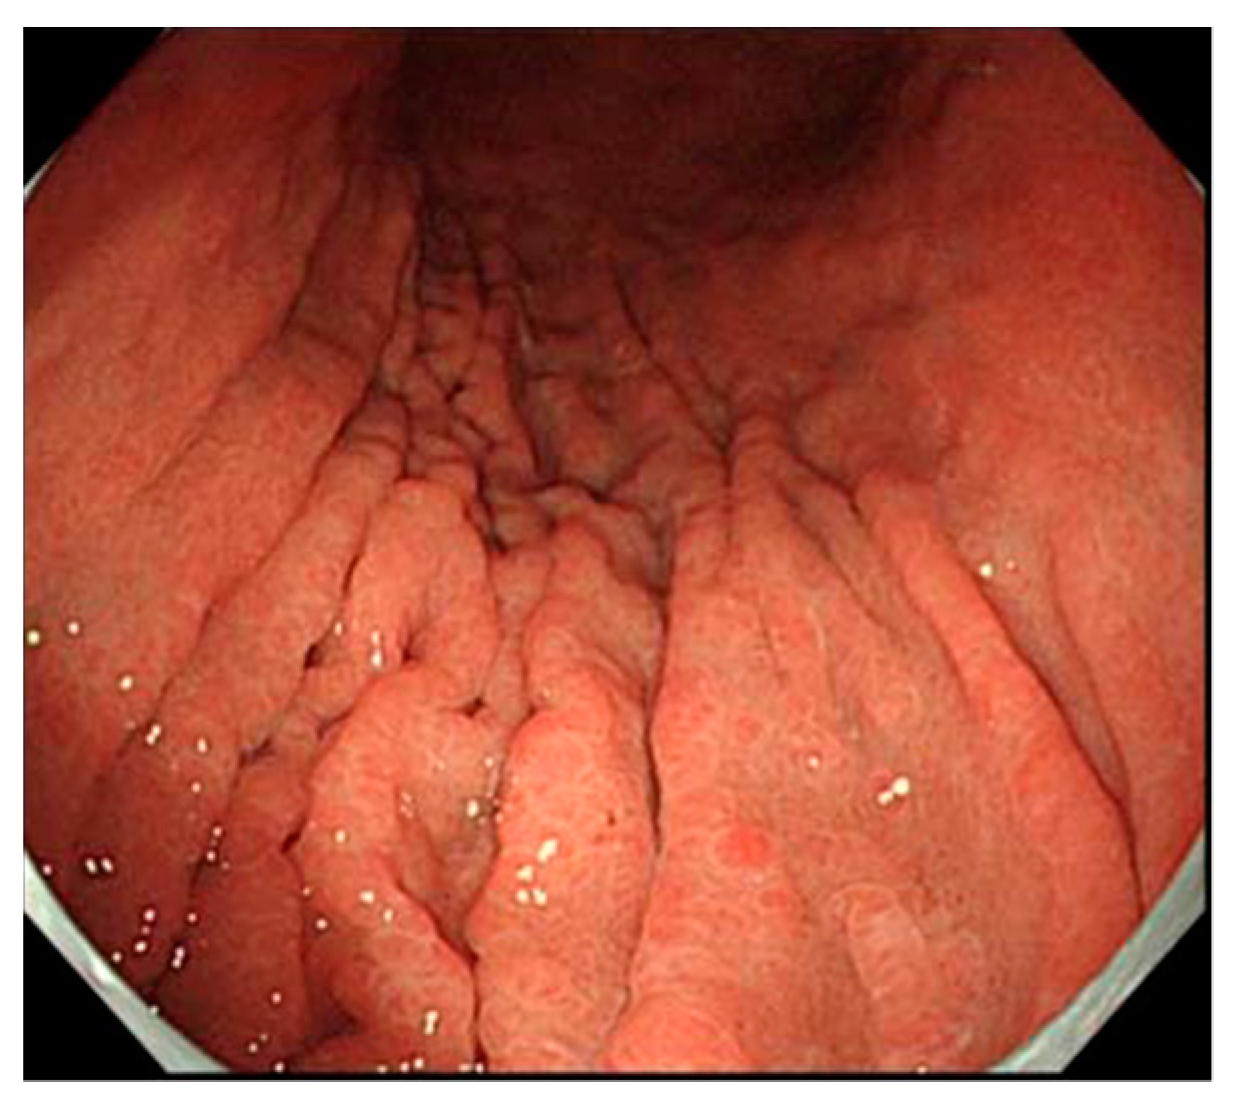

4.2.1. Findings via White Light Observation

- Maruyama, Y.; Kageoka, M. Diagnosis of Type A gastritis. Stomach Intest. 2016, 51, 77–86. (In Japanese) [Google Scholar]

- Kamada, T.; Maruyama, Y.; Monobe, Y.; Haruma, K. Endoscopic features and clinical importance of autoimmune gastritis. Dig. Endosc. 2021, 21, 14175. [Google Scholar] [CrossRef]